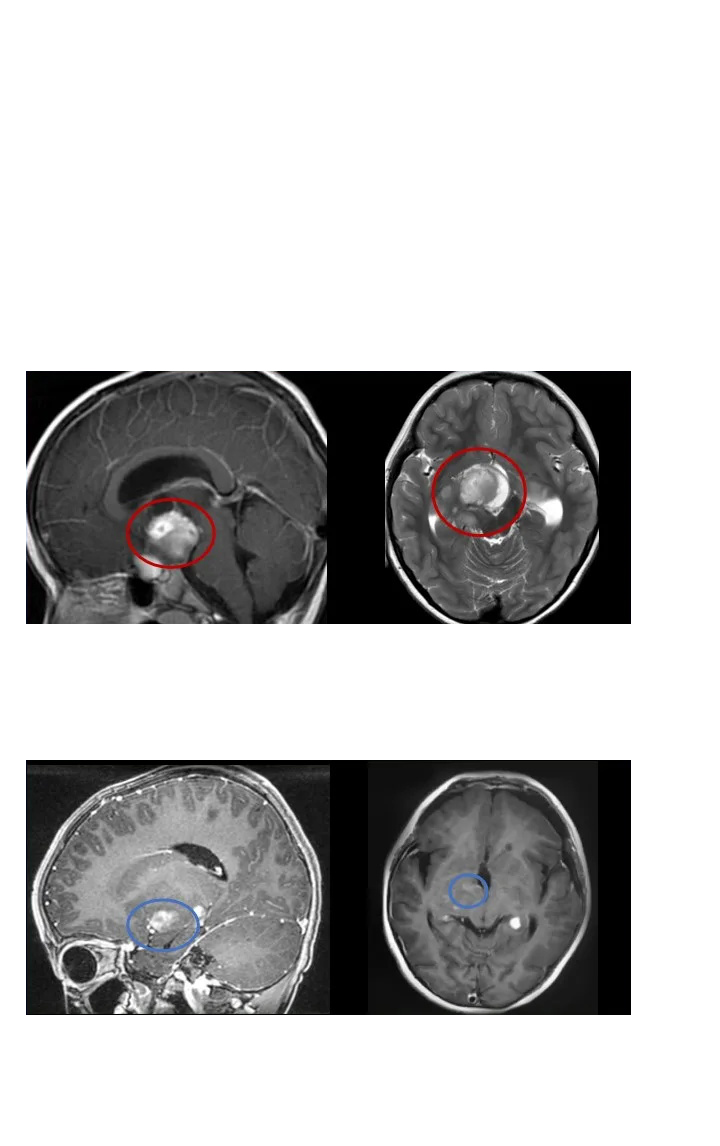

1、50岁男性——脊髓髓内室管膜瘤

病情回顾:50岁的刘先生,2年前因颈部及肩部疼痛就医检查出脊髓髓内肿瘤。由于肿瘤生长在高段颈髓内,被脊骨包围,手术暴露困难,术中脊髓稍受挤压损伤,就可能造成长期性瘫痪。很多医生都建议保守治疗。

手术结果:手术当天,在术中神经电生理监测等高医疗设备辅助下,巴教授顺利全切肿瘤,病例诊断结果为室管膜瘤。术后3天刘先生就可以下地自如行走,术前症状大多已消失,术后无长期性并发症,也无需其他辅助治疗。

2、28岁女性脊髓髓内室管膜瘤,术后3个月恢复正常生活

术前情况:28岁的潇潇6年前开始出现肩部至腰部疼痛,而两年前,潇潇肩部后侧疼痛加剧,于当地医院行磁共振检查,提示髓内占位性病变,保守治疗无效。2021年7月行增强磁共振提示C3水平占位,直径7mm。当地医院排除炎性病变。因考虑到手术风险大,未作手术治疗。2021年10月复查磁共振提示影像较前大致相仿。2022年6月磁共振提示大小约8*12*14mm。2022年10月磁共振提示8*12*19mm。

手术结果:2022年12月4日,苏州独墅湖医院,潇潇的手术顺利进行,巴教授顺利全切潇潇脊髓髓内的肿瘤,术后一天ICU查房,潇潇已经清醒,意识清楚,四肢能够正常活动。教授表示等到术后二天潇潇就可以转入普通病房,一些不舒服的症状,例如手麻等都是正常的,不属于术后并发症,后期能够恢复正常状态。